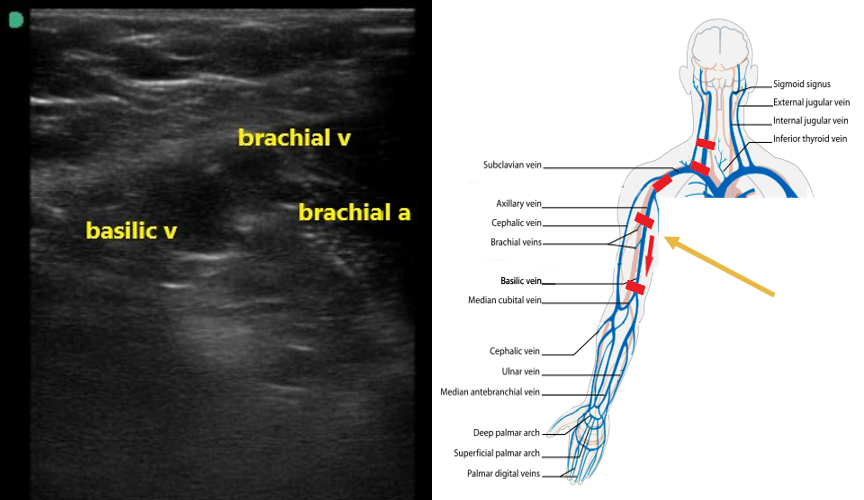

- The axillary vein going distally will split in the proximal humeral region into the basilic and 2 brachial veins (Fig. 7). The brachial veins will be paired with the brachial artery. The basilic vein is larger, more superficial, and runs medially between the biceps and triceps (Video 3).

- Figure 7. Basilic and brachial veins as well as the brachial artery in the proximal upper arm.

Video 3. Axillary vein scanning distally to split into basilic and 2 brachial veins. - Follow these veins to the antecubital fossa, compressing along their course.